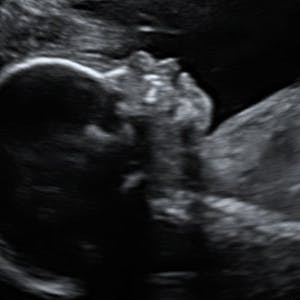

Gravid

Vi gør en dyd ud af at klæde dig godt på både før, under og efter din graviditet. Vi ved, at der kan komme mange spørgsmål til din graviditet, fødsel, amning, din babys udvikling og mange flere emner, derfor har vi samlet guides, tips & tricks samt læsernes egne fortællinger i dette gravid univers.